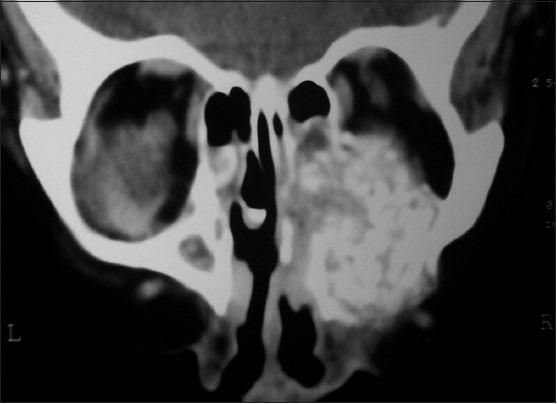

Clear cell variant of calcifying epithelial odontogenic tumor of maxilla: Report of a rare case.

The calcifying epithelial odontogenic tumor (CEOT) is a rare benign tumor of the jaws. Pindborg's tumor having clear cells is extremely rare. Twelve central lesions have been reported of which only three cases have occurred in maxilla. Clear cell variant is a distinct entity, has more aggressive biological behavior and higher chances of recurrence. Hence it is important that presence of clear cells be included in histopathological diagnosis. Here we present a rare case of clear cell CEOT having aggressive behavior.